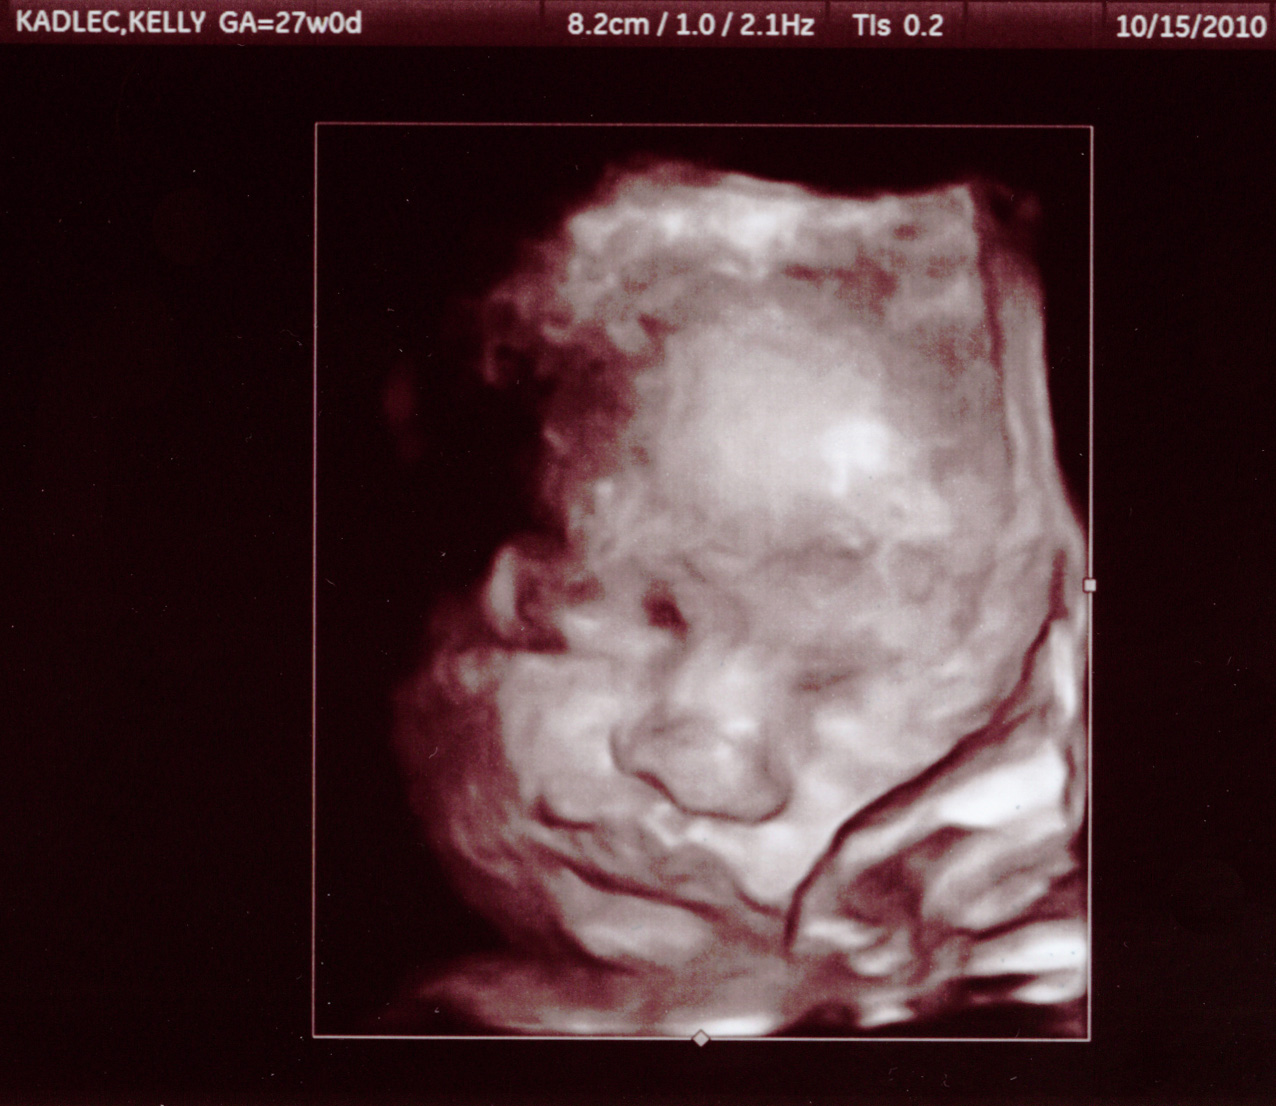

Here are some pictures from our 27 week appointment.